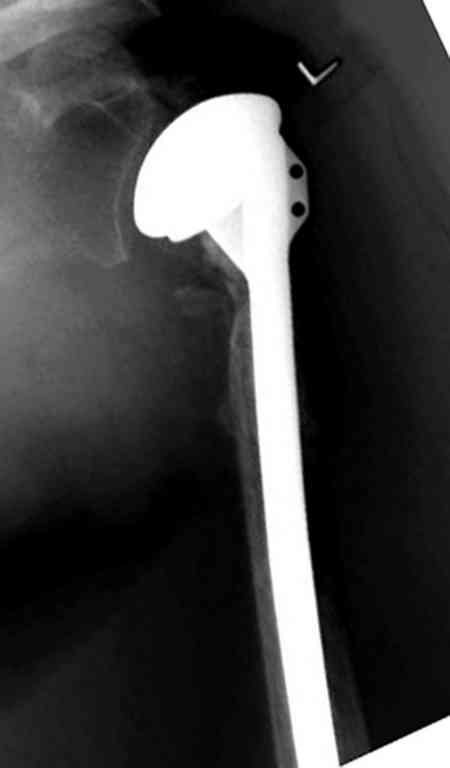

По Neer операцию рекомендовали только тогда, когда угол между диафизом и головкой составляет около 45 градусов, и переломы с меньшим углом смещения считали благоприятным для функционального результата.

Хотя "варусная импакция" в проксимальном отделе плеча срастается хорошо консервативными мерами, но в результате при восстановлении такие больные теряют часть отведения, и тем более у больной варус осложнен еще сгибанием.

Закрытые репозиции без фиксации из-за вторичного смещения неэффективны, поэтому рекомендуется репозиция с фиксацией. Методик много, кто чем владеет и отдает предпочтение закрытые-открытые, перкутанные, с блокирующими пластинами, гвоздь, множественными спицами или методом спиц по Лазареву, и осторожно с манипуляциями из=за возможности повреждения аксиллярного нерва - частый вид осложнении.

Первичное консервативное лечение рекомендуется только тем больным, когда по причинам общего состояния, например, политравма или другие тяжелые состояния больного, не позволяют оперативное лечение при первичном поступлении, тогда такие больные с самого начала предупреждаются о необходимости вальгусной или другой восстановительной операции позднее.

Неправильно выбранная тактика по фиксации или технические ошибки во время операции могут привести к серьезным осложнениям. Здесь привожу

пример из нашей практики, вроде обычный перелом шейки, фиксированный популярным методом "Сиэтла" - множественными спицами 2.8 мм с резьбой на конце.